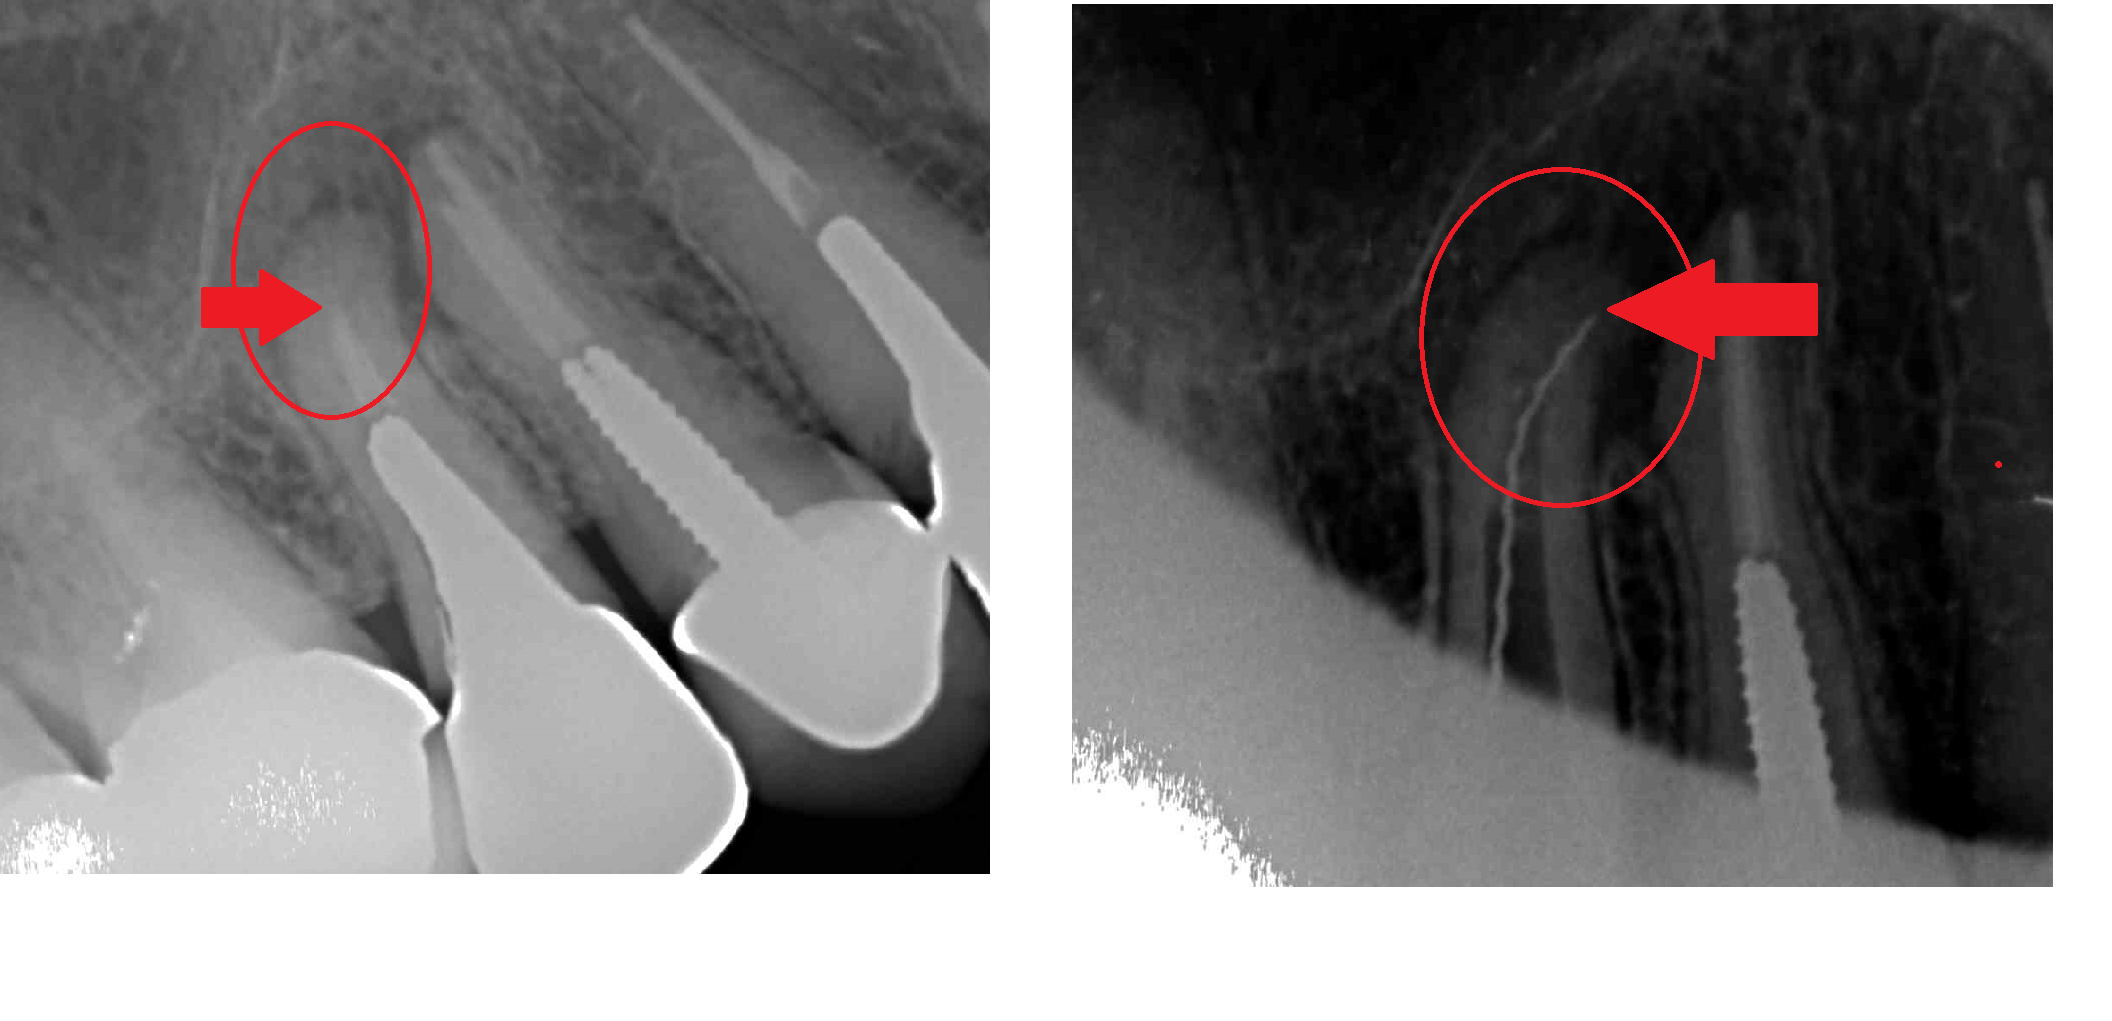

不完全な根の治療

左側写真。根の先端まで治療されずに膿がたまり痛みがあり来院。

右側写真。拡大鏡、マイクロ、マイクロエキスカ使用で、正しい根の位置まで洗浄。

右側写真。拡大鏡、マイクロ、マイクロエキスカ使用で、正しい根の位置まで洗浄。

症状も改善されよかったです。